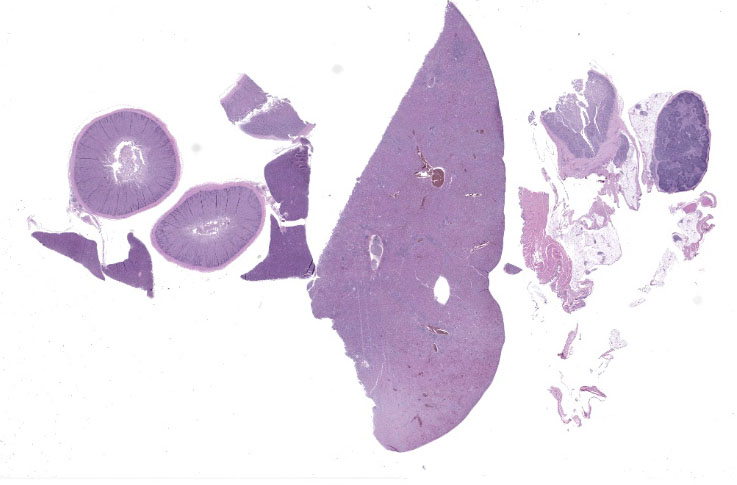

Microscopic Description:

Liver: Surrounding portal regions and occasionally coalescing are infiltrates of moderate numbers of lymphocytes and histiocytes that disrupt the hepatic architecture. Within the lymphocytes and histiocytes are numerous, 2 um in diameter, basophilic protozoal organisms surrounded by a thin, clear halo that peripheralizes the nucleus. The inflammatory cells separate and individualize the hepatocytes, which display mild karyomegaly and frequent binucleation. Free within the sinusoidal lumina and within portal and central veins are numerous, approximately 5 um diameter, pyriform flagellate protozoa with a single, variably distinct nucleus. Occasional large lymphocytes and rare plasma cells circulate throughout the sinusoids.

Duodenum: The mucosal lamina propria is markedly infiltrated and expanded by numerous lymphocytes and histiocytes with rare plasma cells. The inflammatory cells broaden and occasionally fuse the villi and separate the intestinal crypts. Within the mononuclear cells are abundant 2 um diameter, basophilic protozoal organisms surrounded by a thin, clear halo that peripheralizes and indents the nucleus. The crypt epithelial cells are often pyknotic and sloughed into the lumen. Epithelial cells at the crypt bases are often hyperplastic, piling three to four cells thick with increased numbers of mitotic figures. The coelomic fat surrounding the duodenum has small, multifocal aggregates of lymphocytes.

Cloaca, colon, and bursa of Fabricius: The lamina propria of the colon is infiltrated and expanded by moderate numbers of lymphocytes and plasma cells that separate colonic crypts. Multifocal crypts are filled with numerous, approximately 5 um diameter, pyriform flagellates with a single, variably distinct nucleus. Similar flagellates are also identified in large numbers within the lumen. Within the bursa of Fabricius, there are similar trichomonad flagellates as well as approximately 2-3 um diameter, round, protozoal organisms that are often adhered to the superficial surface of the epithelial cells.

Liver: Moderate, multifocal, chronic, lymphohistiocytic hepatitis with intracellular protozoa (consistent with isosporosis, Isospora sp) and sinusoidal flagellates

Duodenum: severe, chronic, segmental, histiocytic enteritis, with abundant intracellular protozoa (consistent with isosporosis, Isospora sp.)

Cloaca and bursa of Fabricius: moderate, chronic, proliferative and lymphoplasmacytic cloacitis and bursitis with superficial mucosal protozoa, consistent with cryptosporidiosis, Cryptosporidium sp.

Colon and cloaca: myriad crypt and luminal flagellates

1. Liver: Cholangiohepatitis, histiocytic and lymphoplasmacytic, chronic, diffuse, marked, with intrahistiocytic apicomplexan zoites and sinusoidal flagellates.

2. Duodenum: Enteritis, histiocytic, chronic, diffuse, severe, with intrahistiocytic apicomplexan zoites.

3. Cloaca: Cloacitis, proliferative and histiocytic, chronic, diffuse, marked, with numerous luminal flagellates.

4. Bursa of Fabricius: Bursitis, necrotizing, chronic, multifocal, mild, with intraluminal flagellates.